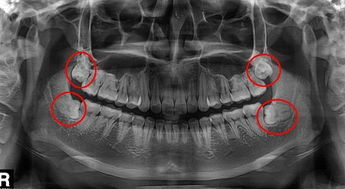

智齒位於(yu) 牙列末端,從(cong) 門牙開始向後數的第8顆牙齒,拍片後4顆智齒清楚顯示如上圖